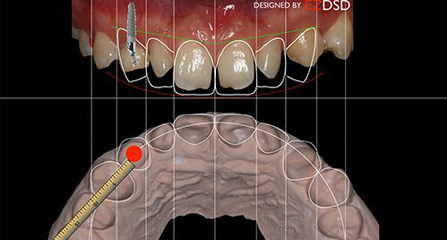

麦芽口腔着眼于全链条的数字化诊疗解决方案,与德国Kavo、瑞典Nobel、韩国奥齿泰、中国康泰健等国际知名齿科品牌合作,建立“深圳数字化口腔联盟”,应用全数字化口腔模式,从CBCT数据提取、AI口扫取模、AI智能口腔体检、数字化分析模拟与方案设计、3D打印、CAD/CAM椅旁加工以及手术模拟导航等,全流程打通数字化口腔精确诊疗的各个环节,实现麦芽数字化口腔诊疗体系新升级。

DSD精确设计 专属黄金迷人微笑